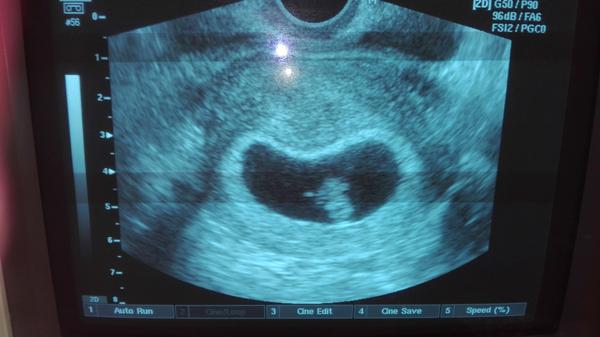

Ahojte tak aj ja posielam prvu fotku nasho miniho 🙂 srdiecko pekne bije, tiez mi doktor este nepovedal presný týžden, o tri týždne kontrola a da mi aj preukaz. beriem tiez prohesteron kvoli rozhadzaným cyklom, brala som uz ho uz asi 4 mesiace pre otehotnenim, lebo som obcas ani ovulku nemala. no a nakoniec vsetko dobre dopadlo a tesime sa na drobca 🙂